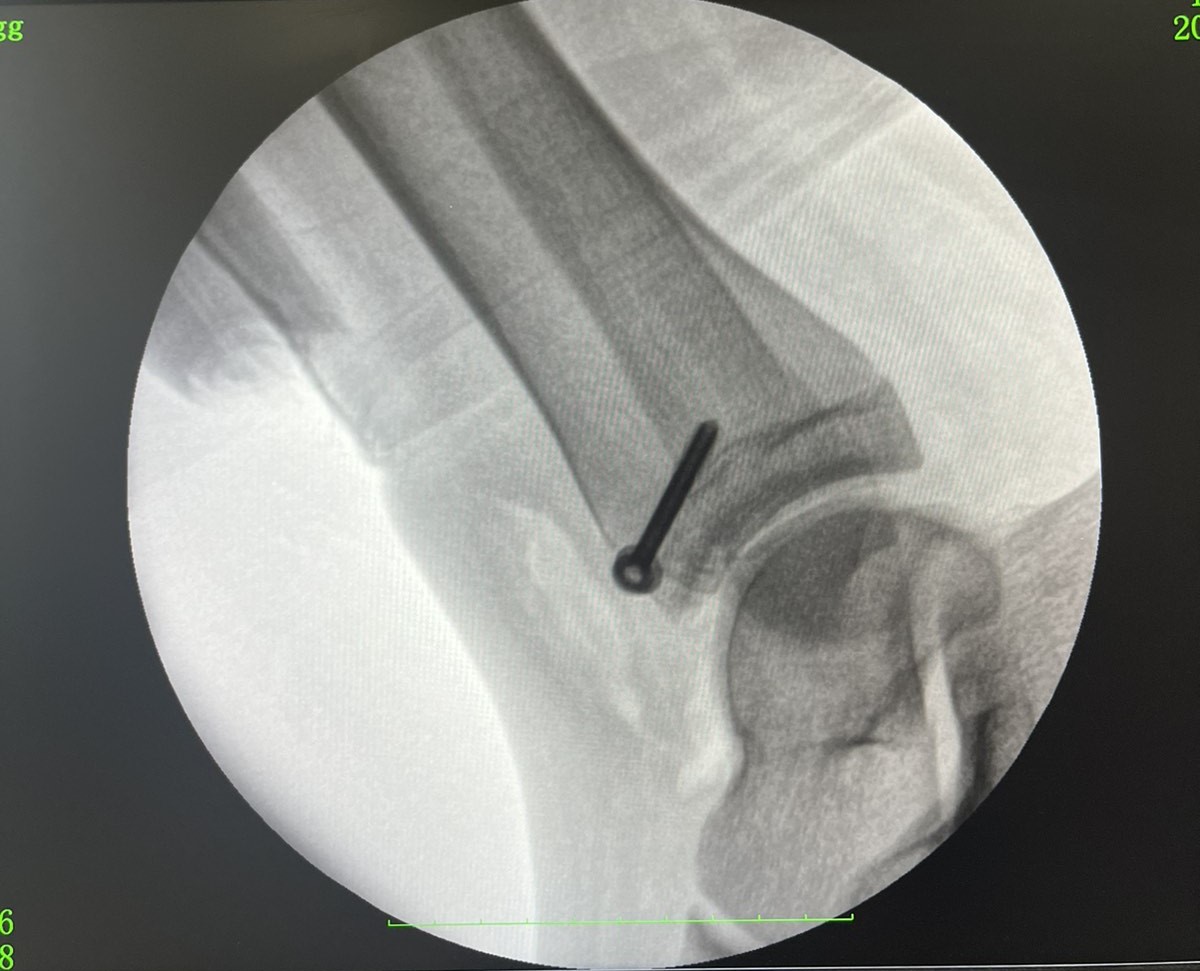

Пациентку госпитализировали в ортопедо-травматологический центр больницы с переломом большеберцовой кости, которому было уже две недели. С помощью рентгенографии удалось определить, что это был редкий перелом Тилло.

По словам медиков, этот вид перелома возникает вследствие излишней наружной ротации в голеностопном суставе. Он приводит не только к деформации кости, но и к повреждению передне-нижней большеберцовой связки.

Отмечается, что для лечения перелома Тилло используется методика открытой репозиции и фиксации титановым винтом. После операции полное восстановление функции голеностопного сустава занимает от 6 до 12 месяцев.

Перелом Тилло (фото: facebook.com/RivneODL)

Как выглядит нога после операции (фото: facebook.com/RivneODL)